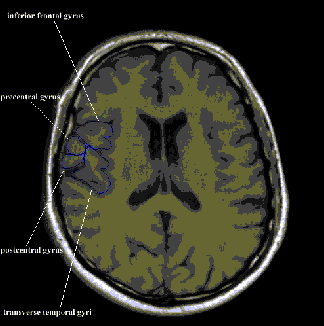

Figure 2. An example of the Tampere Brain Atlas to illustrate a brain infarct in the

right a.cerebri media lesioning inferior frontal gyrus, both precentral and postcentral gyri and inferior parietal

gyrus.